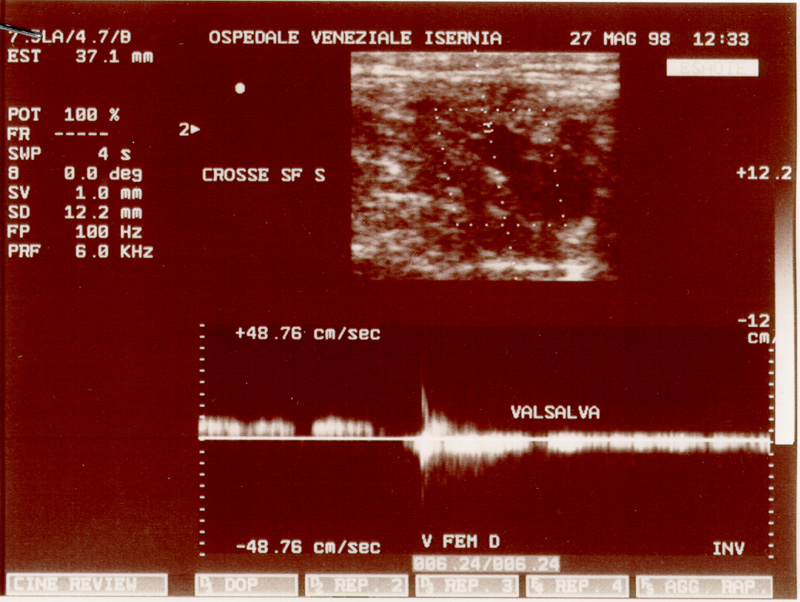

Nel maggio del 98 Maddalena viene ricoverata all'Ospedale di Isernia, per un sospetto virus allo stomaco, la terapia non dà alcun risultato. L'8 luglio viene urgentemente ricoverata all'Ospedale di Agnone. Si scopre un carcinoma invasivo al pancreas. E' colta dalla signora MORTE il 30 agosto 1998 alle cinque ed un quarto del mattino. Il calendario festeggia Santa Tecla. Due giorni dopo invece, se fosse stata in vita, sarebbe ricorso il 47esimo anno di matrimonio. E' morta alla stessa ora in cui era nata. Alle cinque del mattino.